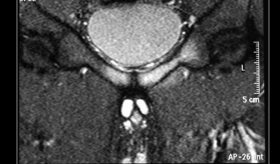

Con el fin de caracterizar mejor la lesión, se solicitó una resonancia magnética pélvica. Las imágenes mostraron una lesión bien circunscrita y realzada de 1,7 × 1,4 cm, predominantemente intraluminal, localizada en la uretra distal con extensión hacia la pared vaginal anterior, pero sin evidencia de invasión tisular profunda ni afectación de órganos vecinos. La uretra proximal no mostraba alteraciones y no se evidenciaron hallazgos sugestivos de malignidad.

La evaluación por resonancia magnética permite determinar con precisión la localización y las características del tumor, y es útil para descartar malignidad. El diagnóstico definitivo, no obstante, se establece mediante el análisis histológico, que evidencia células fusiformes benignas sin signos de atipia.